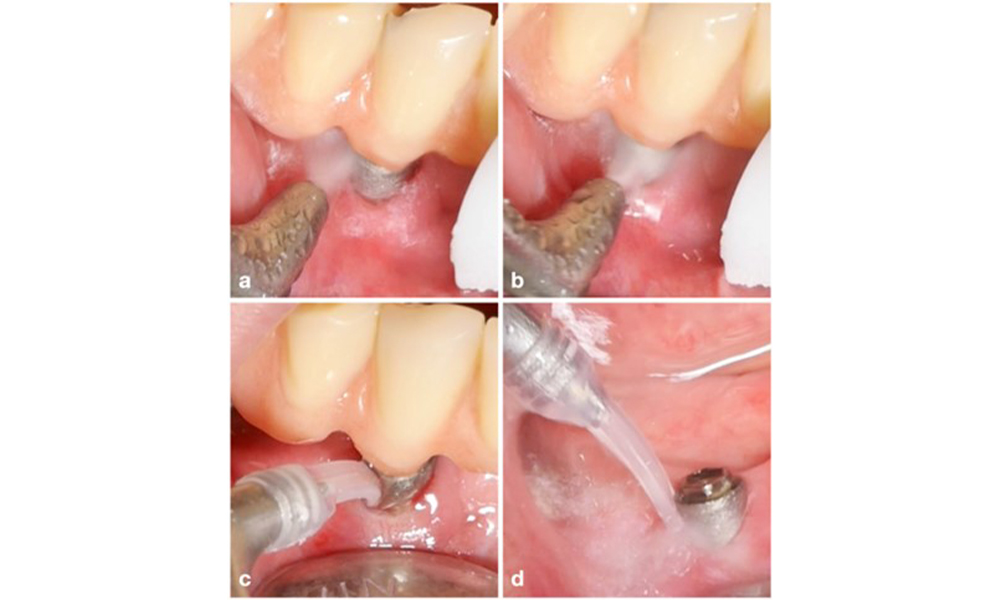

Management of peri-implantitis at implants judged as treatable consists of a non-surgical phase, which is often followed by surgical intervention. For the non-surgical approach, similar measures as those applied for the treatment of peri-implant mucositis are used; based on laboratory experiments air-polishing devices with a subgingival nozzle appear to provide certain advantages in terms of biofilm removal, compared to hand- or ultrasonic instruments (Herrera et al. 2023; Moharrami et al. 2019; Ronay et al. 2017) (figure 9).